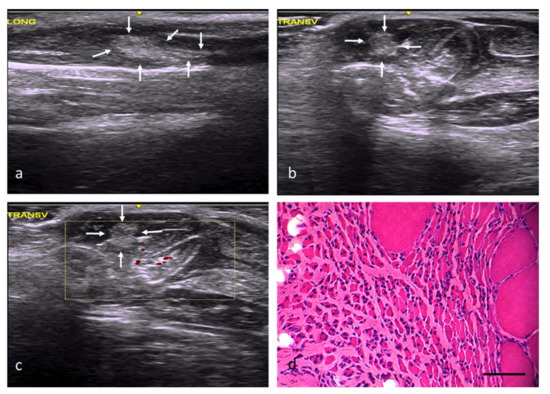

| Group | Identification of the Lesion | Edges of Lesion | Morphology of the Lesion | Increased Echogenicity | Echotexture Distortion | Vascularization |

|---|---|---|---|---|---|---|

| NC | — | — | — | Grade 0 | Grade 0 | Grade 0 |

| RC | Yes | poorly delimited | imprecise | Grade 1 | Grade 1 | Perilesional Grade 2 |

| FC | Yes | well delimited | angulated | Grade 3 | Grade 3 | Intralesional Grade 2 |

| AT | Yes | poorly delimited | imprecise | Grade 2 | Grade 1 | Intralesional Grade 1 |

| OS | Yes | well delimited | Variable (rounded, angled, or patchy) | Grade 3 | Grade 3 | Perilesional Grade 1 |

| DM | Yes | well delimited | Variable (rounded, angled, or patchy) | Grade 2 | Grade 3 | Intralesional Grade 1 |